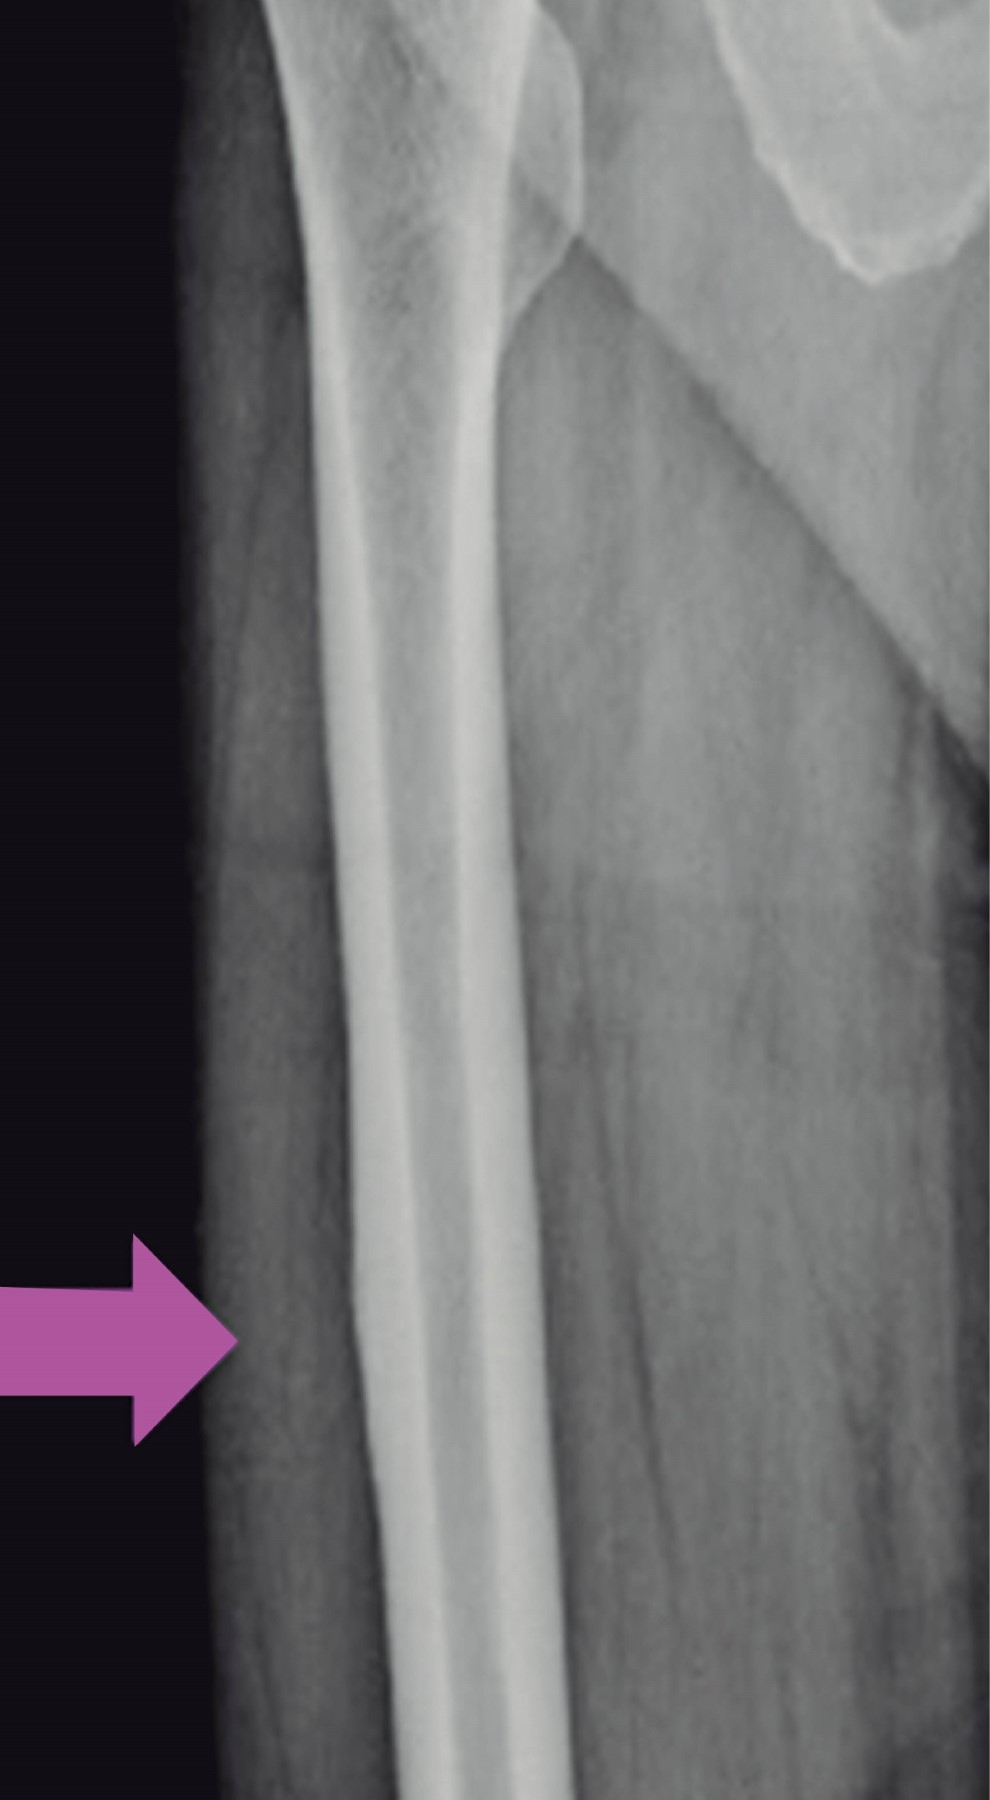

An 83-year-old female with a 10-year history of bisphosphonate treatment for osteoporosis (alendronic acid, 70 mg presentation), came to the orthopedic consult after feeling leg pain. Normal movement, with limitation and instability, while standing up. An X-ray and CT scan of the pelvis were obtained. Figure 1 shows the thickening of the bone cortex, with the presence of atypical incomplete bilateral fractures in the subtrochanteric femur. After a complete assessment, the patient underwent surgical treatment with intramedullary nailing (Figure 2), and thromboprophylaxis with Apixaban 2.5 mg every 12 hours for 28 days was indicated.

A 76-year-old female patient used alendronate for four consecutive years, switching afterward to zoledronic acid and using it for five more years, making it a total of nine years of BISPH use. She arrived at the emergency room after experiencing a spontaneous fracture of the left femur while taking a walk (Figure 3), leading to a fall from her height. The clinical examination and radiographs demonstrated a left Atypical Femur Fracture (AFF). Upon further observation, an incomplete fracture was found in the right femur (Figure 4). She underwent a first surgical intervention, and two days later, a second one; intramedullary nailing was performed in both femurs (Figure 5). A lumbar spine dual-energy X-ray absorptiometry (DEXA) was performed, which reported a T Score of −0.9, spine TBS of 1.382, left femoral neck T-score of −1.5, and right femoral neck T-score of −1.7, leading to an osteopenia diagnosis.